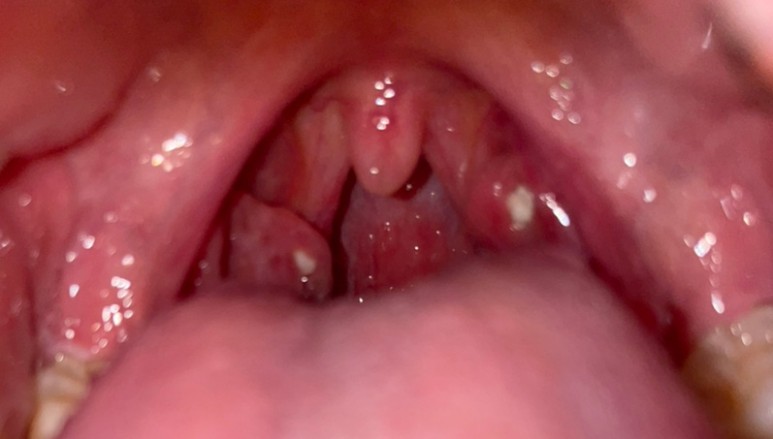

수술 끝나고 병실에 왔는데 너무 추웠어. 벌벌 떨면서 잠이 들었다.눈을 뜨고 나서 원장님이 오셔서 수술은 잘 되었다고 생각하는 결석뿐만 아니라 안쪽에도 결석도 많고 편도가 많이 커졌고 염증도 심해서 좋지 않았던 상태라는 것.. 흑우.. 눈을 뜨자마자 미친듯이 목이 아픈 누군가가 내 목젓을 손으로 감싸 꽉 쥐고 있는 느낌.. 침을 삼킬 때마다 한번씩 짜내는 느낌.. 너무 아파.. 수술한 뒤 오후 4시 30분 이후부터 물을 조금씩 먹으라고 한 물을 마셨는데..아파서 한 번 먹고 안마 저녁도 죽 나왔는데 못 먹겠다…

수술이 끝나고 회복실에 있었는데.. 그때도 속이 울렁거리면서 구토한 회복실 간호사가 허겁지겁 누군가에게 연락했고, 나는 다시 기분이 좋아지는 주사를 맞았다는 것.주사를 맞고 병실로 이동하다.미친 듯이 아팠어… 목을 누군가가 바늘로 찌르는 느낌.제 수술 담당 의사와 교수님이 따로 방문하셔서 목을 보면서 수술 부위 안쪽에 출혈이 생겼다고 하셨다.제가 생각하기에는 수술이 잘못된 것보다는 기침을 하면서 자극이 생겼기 때문이라고 생각한 교수님께서도 말씀하시기에는 10000분의 1확률에 걸린 것 같다고 하셨고… (결국 운이 나빴다고 하시는데…) 제 길) 2박3일 입원해 있으면 된다고 하시는데 또 출혈이 생길 수 있다고 해서 금요일까지 입원하기로 했다.저는 일주일도 안돼서 전신마취 두번하고 수술도 두번 했다는 점에서..

아침에 간호사 선생님이 혈압을 측정하면서 7시 반에 이비인후과 외래 진료를 받아야 한다고 하셨다. 7시 20분에 출발해 도착해 진료를 보니 피가 조금 고여 있다고 한다. 어젯밤에 양치질을 할 때 피가 좀 난 것을 말한다. 내일 퇴원하는데 가능한가요? 들어보니 내일 다시 진료를 받아보고 협의하자고 하셨다. 아침에 일어날 때가 통증이 가장 심하다…저녁에는 자고 잘 모르는 통증이 아침에 한꺼번에 나타나는 것 같은…이비인후과를 다녀와서 간호사실에 진통제를 놓아달라고 한다.이번엔 엉덩이 주사 맞고 쉬고 돌아다니기로 한 (나는 매일 진통제로 버티는 것 같다) 교수 말대로 축축해져서 더 그럴지도 모른다.길래병원을 돌아다니며 구경함대병원은 이렇게 큰지 다시 한번 생각하며 돌아다닌 편의점에 가서 아이스크림도 사먹는다.내가 편도수술을 할 때 최고의 아이스크림은 파랗게 먹으면 나타나는 소다맛 아이스크림이었다!부드럽고 자극적이지 않고 달콤하다.그렇게 마지막 밤이라고 생각하고 잠이 들었어!!

전날 마지막날 사진을 찍는다!! 아침에 일어나 오늘도 이비인후과 진료를 받았다.진찰을 받았는데 큰 이상은 없는데 통증이 있는데 내일 퇴원할까요?라고 물었는데 오늘 퇴원하고 싶었다.씻고 싶었다…. 그래서 오늘 퇴원하기로 했다!! 퇴원약을 처방해준다고 하니 일주일치에서 진통제 제일 강한 것, 그리고 기침약 소화제 꼭 주세요”라고 하자 다시 병실로 가던 중 간호사실에 들러 진통제를 해달라고 한다. 작은 진통제가 계속 들어가 있는데 나는 왠지 그거 효과가 없는 것 같다 24시간 250ml 4개씩 맞는데 효과가 없는 것 같다… 마지막 엉덩이 주사로 진통제를 맞은 후 수액을 다 빼주세요.11시 이전에 보험심사가 완료된다고 해서 기다리는데 10시50분에 심사완료..퇴원수속을 하고 서류를 고르는 데 1시간이 걸린다.진통제의 힘으로 버티고 사무실에 가서 병가를 내고 밀린 일을 조금 하다가 긱사로 가서 쉬고 KTX를 타고 광주로 갔다.아버지가 데리러 와서 벨라에 들러 얼음약을 사서 집으로 향했다.